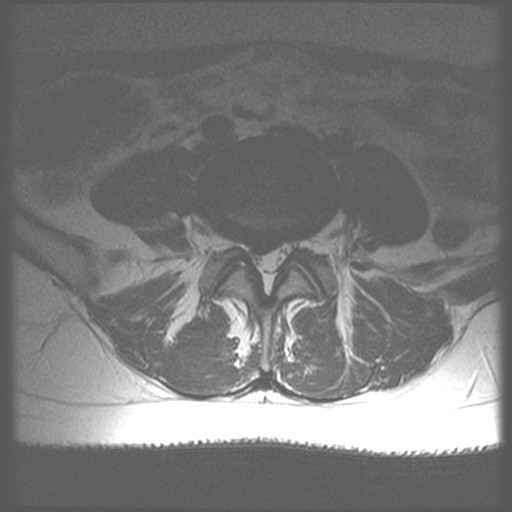

bekken